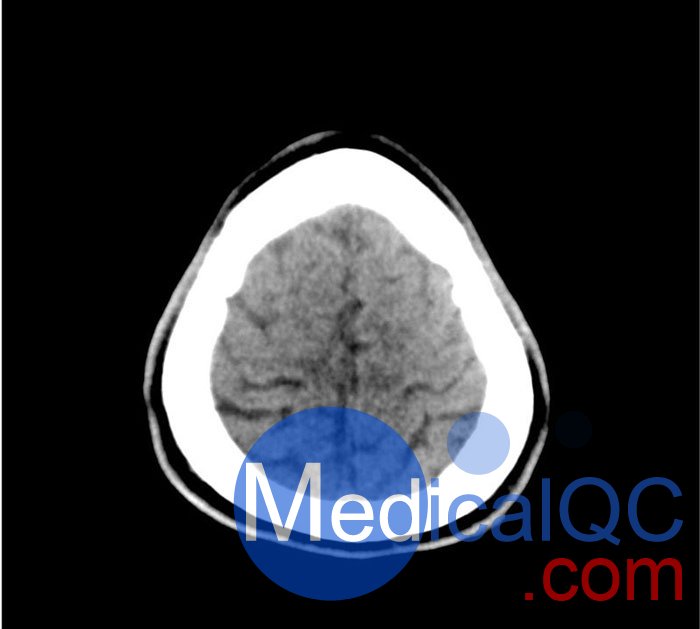

50-01頭部CT模體,50-01腦中風(fēng)頭部模體,50-01腦出血頭部模體模擬了具有中風(fēng)和出血模式的頭部。它覆蓋枕骨大孔的頂點(diǎn)。

卒中模式包括早期梗死的體征(大腦中動(dòng)脈高密度、基底神經(jīng)節(jié)消失)、急性和亞急性分水嶺梗死以及不同年齡的腔隙性梗死。

出血模式包括蛛網(wǎng)膜下腔出血、不同年齡的硬膜下出血、腦室內(nèi)出血和腦出血。

該模型可用于 CT(包括 CBCT)以評(píng)估和優(yōu)化成像性能和 AI 支持的診斷。它也適用于培訓(xùn)目的。

該模型提供了對(duì)常見大腦病理、軟組織和骨組織的詳細(xì)而逼真的模擬??諝饪障短畛溆屑s-160HU的纖維素-聚合物復(fù)合材料。

50-01頭部CT模體,50-01腦中風(fēng)頭部模體,50-01腦出血頭部模體影像效果圖: